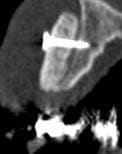

Je me permets de vous soumettre les clichés de scan à 5 mois d'une greffe d'apposition maxillaire antérieure secteur 11 12 que j'ai réalisée.

J'avoue avoir été surprise du hiatus qui existe encore entre greffon et os cortical initial, je suis d'ailleurs déçue je pensais que la forme que j'avais donnée permettait un meilleur "placage" du dit greffon.

D'après vous est ce que cette image est trop précoce dans le processus de cica et que mon "vide" va se combler dans les semainesà venir? je note bien l'intégration sur la crête et les bordures de la greffe.

ta 5 em coupe est pas si mal

sur la coupe 1 et 2 on percoit encore la corticale presqu'intact... on doit enclaver le bloc donneur dans l'os receveur

Il faut un contact intime du greffon avec le site receveur et ici cela ne devait pas être le cas sur toute la surface. Mais une partie semble bien minéralisée. Attends encore un mois avant d'intervenir, tu verras bien à ce moment là.

Je dois dire que quand j'ai reçu les images du scan j'ai fait défilé les coupes horizontales de cervical en apical et là j'étais ravie : on ne voyait cette maladaptation que dans une faible zone au tiers apical dans le creux de la concavité de 13. C'est après que j'ai déchanté.

Quand je fais circuler ma souris sur le logiciel de planification sur les zones "sombres" le logiciel m'indique une densité assez correcte très proche de celle de l'os spongieux du patient,du coup je me dis que la minéralisation est en cours....

Pourtant à partir de la coupe 142 on commence à voir une belle fusion entre les 2 surfaces.